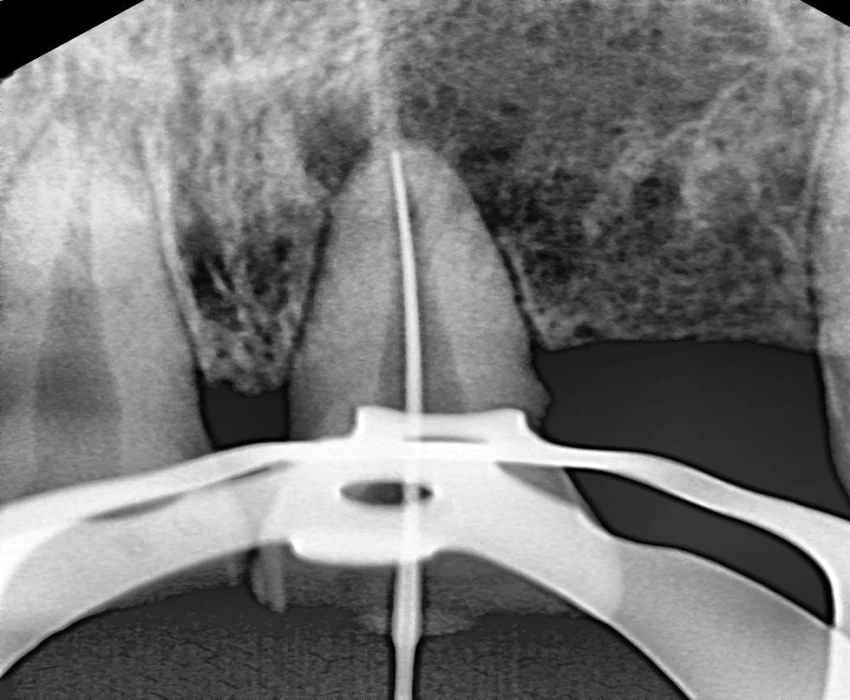

Investigation- CBCT, Viral markers, CBC, BT, CT

DIAGNOSIS- irreversible pulpitis with periapical granuloma.

TREATMENT- Faulty prosthesis is removed in respect to 22, with the help of tapered fissure. Access Opening is done' in respect to 21, under La. Working length is determined . Canals are prepared using Hyflex CM and obturated using Gutta percha using lateral condensation. Microperiosteal flap is raised. Window preparation irt 21 , periapical curretage apicoectomy is done irt 21 followed by retrograde filling with bioceramic. Cavity is filled with bone graft. Sutures placed.